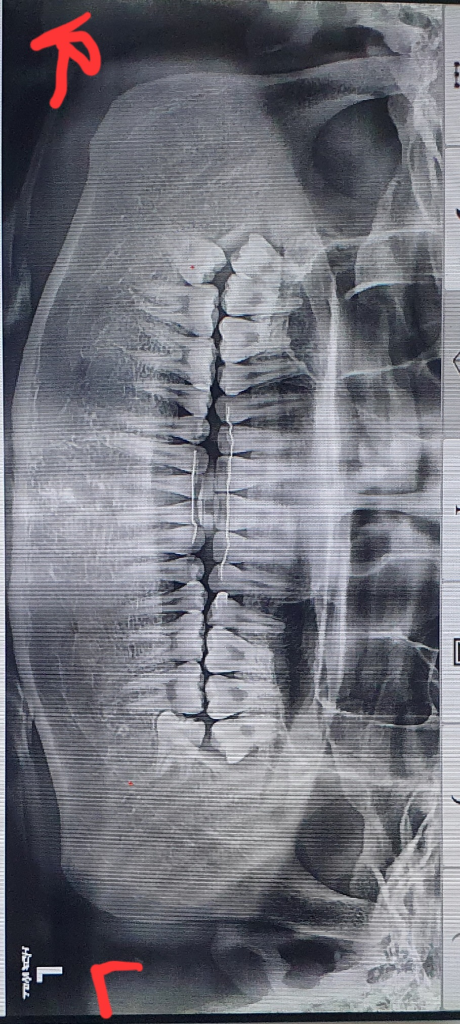

교합이 기울어졌는데 어떻게 해야 될까요?

10년전 발치교정을 했고

성인인 현재 하악이 기울어지고 (어금니가 기울어진것 같기도 합니다) 전체적인 안면비대칭이 심합니다 지금 시험을 준비하고 있어서 거리든 비용문제든 교정전문 치과를 당장 다니기는 힘든 상황입니다 그래서 1년뒤에나 교정할수 있을 것 같은데

개방교합 있고요

맨밑 사진은 사랑니 발치전 2년전 사진이라 교합이 좀 다를 수 있습니다